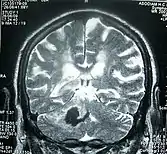

Perinatal stroke can be diagnosed with medical imaging techniques that present the brain's image. The usage of diffusion-weighted imaging (DW MRI) with magnetic resonance imaging (MRI) is effective for early diagnosis of perinatal stroke.[18] Computerized tomography (CT) is also a commonly used diagnostic technique for this disease.[36] These medical imaging techniques can show bleeding or blockage in the brain and detect damage caused by ischemic stroke or hemorrhages to the brain tissues.[37] The use of MRI is clinically preferred as opposed to CT as it can highlight the brain’s blood flow.[36] In addition, perinatal stroke is challenging to classify on CT as the neonatal brain has higher water content.[7][37] However, in certain situations, such as the inability to transport unstable infants with severe respiratory or cardiac disorders from the ICU, cranial ultrasound (CUS) is used as an alternative to MRI.[7] CUS can identify intracranial hemorrhage (ICH), intraventricular hemorrhage (IVH), large cerebral sinus venous thrombosis (CSVT) along with the brain’s blood flow.[7]